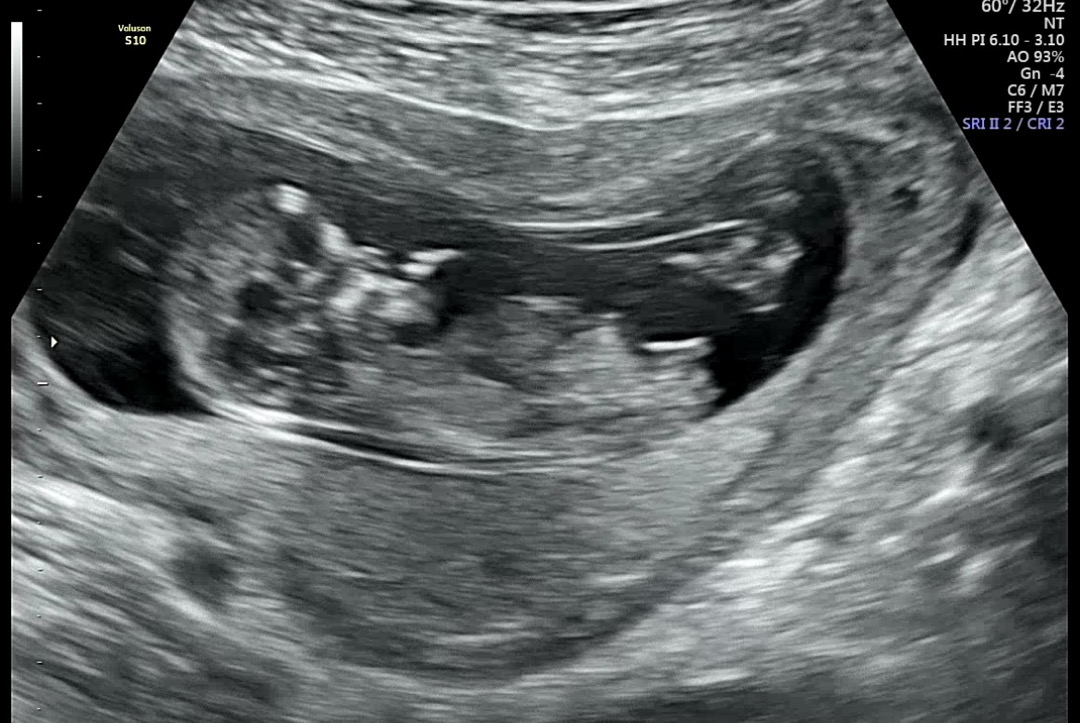

각도법 고수님들 한번맘 봐주세요!

둘짼데 저는 봐도 잘 모르겠어서요 🥹 알려쥬세요...🥹 12주2일이예요!